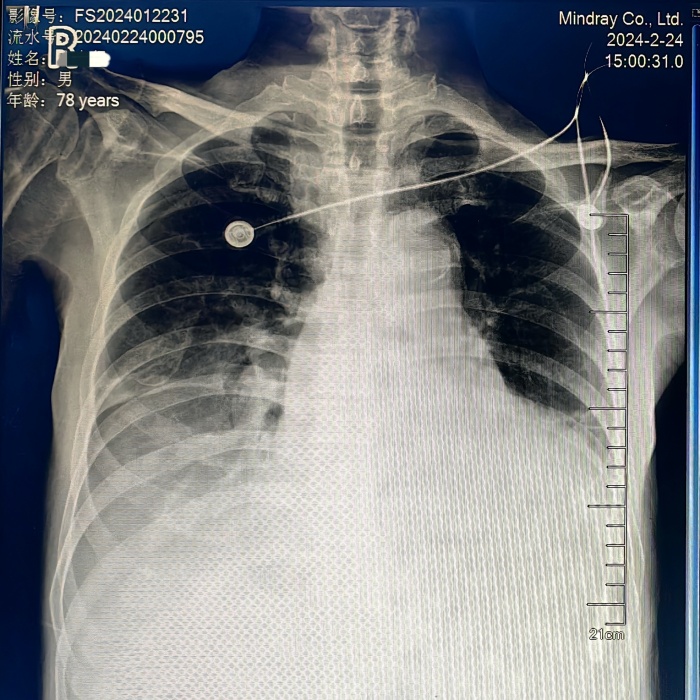

好景不长,外院刚出院不久,老唐又因“心衰”发作于2月21日入住医院心血管内科,床旁心脏超声提示:主动脉瓣重度关闭不全,合并有二尖瓣中-重度关闭不全,三尖瓣中-重度关闭不全,升主动脉增宽。动脉血气分析提示II型呼吸衰竭、高碳酸血症、高钾血症、乳酸酸中毒等,病情十分危重,患者胸闷、气促心衰症状明显,正常呼吸都费劲,不能平躺休息,意识状态迷糊,无尿,经药物治疗后症状缓解不明显,随时有可能出现呼吸心脏骤停,经重症医学科会诊后有紧急气管插管指征(有创呼吸机辅助呼吸),老唐此刻命悬一线!

家属性命相托,医生全力以赴。在充分的术前准备下,潘禹辰主任团队在短时间内顺利为老唐进行了微创经导管主动脉瓣置换手术(TAVR),给患者置换了一个新的“心门”。手术过程惊心动魄,大瓣环纯返流,窦部及升主动脉扩张,术中难以锚定瓣膜,先后经历更换导丝、更换瓣膜、五次释放才将人工瓣膜精准释放到位。

老唐的术后康复之路也十分坎坷,先后经历了一系列惊心动魄的抢救和治疗(II型呼吸衰竭需要再次气管插管、肾功能损害加重需要连夜紧急床旁血液透析、III°房室传导阻滞需要安装心脏永久起搏器、贫血、血小板减少等),抢救过程步步惊心。